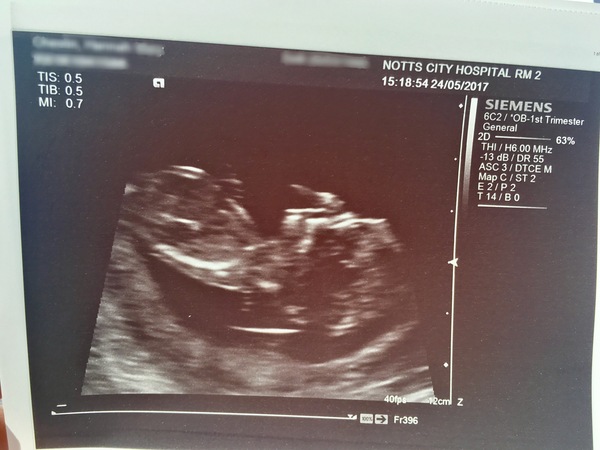

MontyPants · 24/05/2017 18:48

It's a baby! 😁 Feeling a lot calmer now. They weren't able to measure the fluid behind its neck because it wouldn't move to the correct position. I have a stubborn baby. But the sonographer couldn't see any abnormalities, so all is good. Thanks for the calming messages all.

Great scan Monty!! A proper baby :)

Yay congrats monty! Seems you had the same as me yesterday - stubborn baby preventing a nuchal measurement. I was there for ages! Did they make you jump up and down?